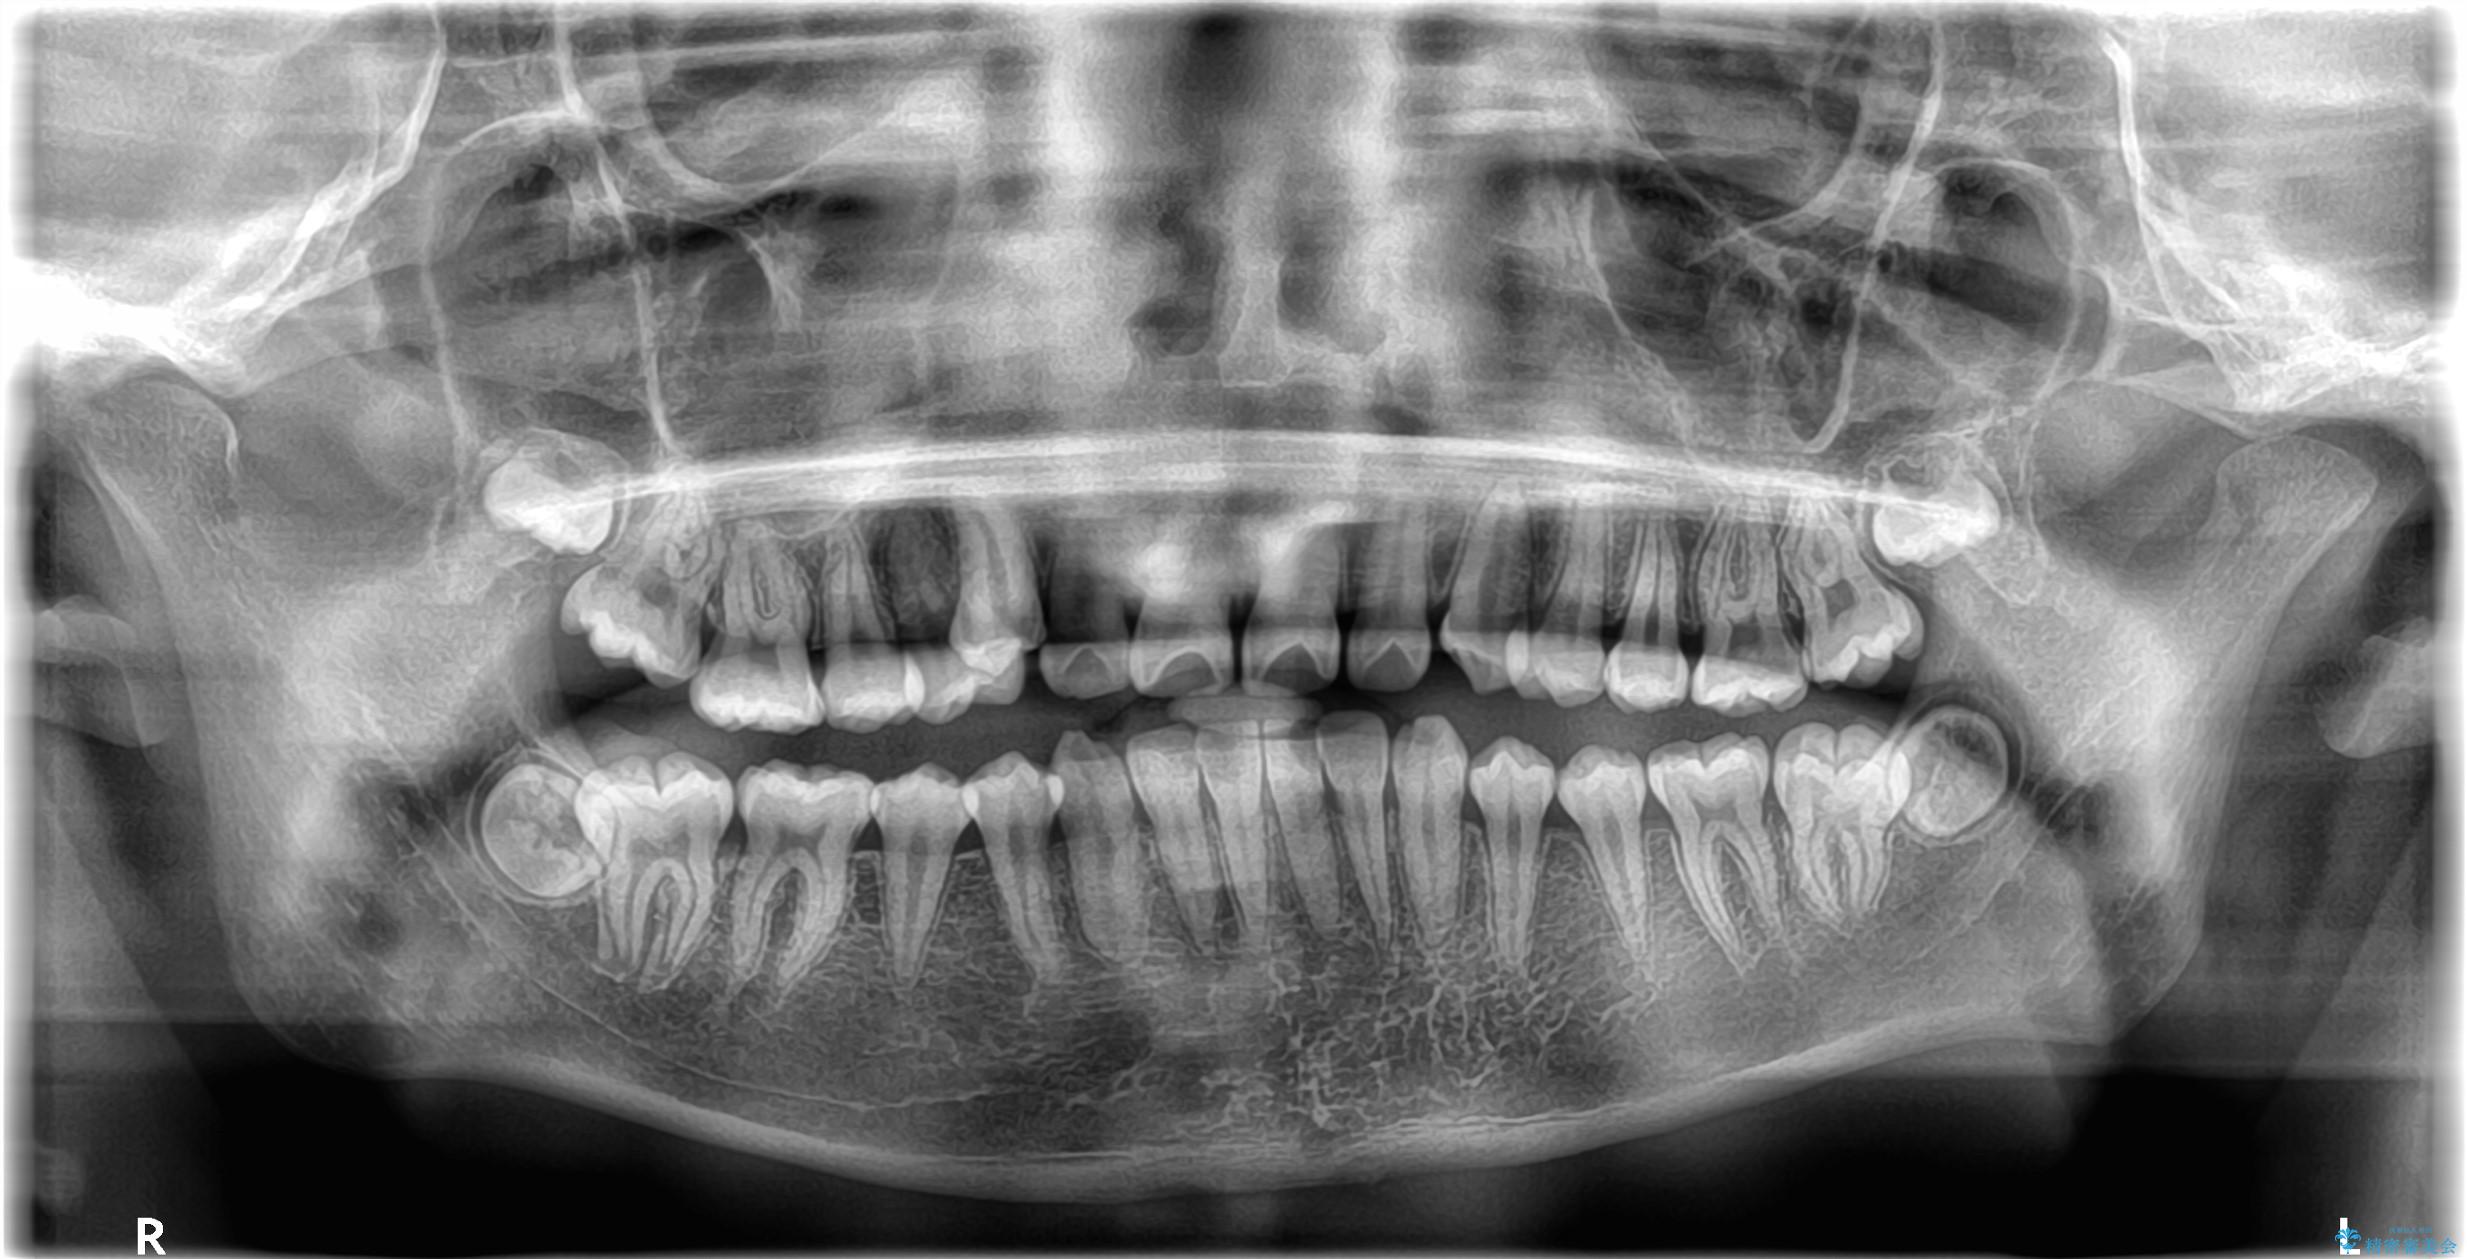

矯正の精密検査の結果上顎左右4番の計2本を抜歯し、審美性に配慮したワイヤー矯正装置(審美装置)を用いて治療を行いました。

八重歯などの歯列のデコボコが綺麗に改善され、患者様にも大変喜んでいただけました。また、咬み合わせが深い「ディープバイト」も併せて改善し、見た目だけでなく機能面でもバランスの取れた咬合を獲得しています。